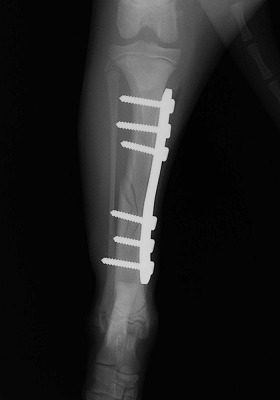

家の中で遊んでいると「キャイーン」という悲鳴と共に片方の足を地面に付く事が出来なくなり来院されました。レントゲンを撮り調べてみると骨折していることが判明。

手術をして元の状態に骨を整復しました。